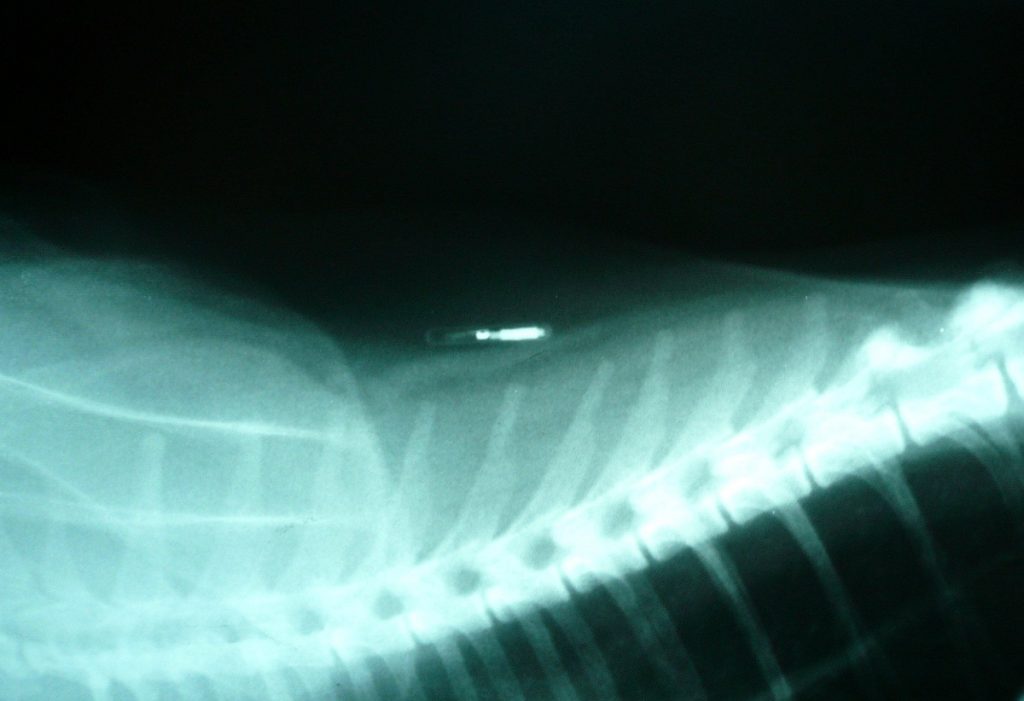

Чіп (транспондер, мікрочіп) є електронною мікросхемою зі стандартним розміром 12х2 мм або в міні варіанті ― 8х1,4 мм. Прилад має приймач сигналу, його передавач та блок, що містить інформацію про тварину та господаря. Кожен чіп має унікальний код, що складається з 15 знаків і закріплений за конкретним котом до кінця його життя. Відразу після чіпування код вносять до спеціальної світової бази даних.

Пристрій абсолютно безпечний для здоров’я кішки. Мікросхема знаходиться в стерильній капсулі, виготовленій із біосумісного матеріалу. Згодом капсула обростає сполучною тканиною на зразок штифта або імпланта і стає частиною тіла тварини.

- введення під шкіру в ділянці холки / загривка розчину з чіпом;

- перевірка реакції пристрою сканером;